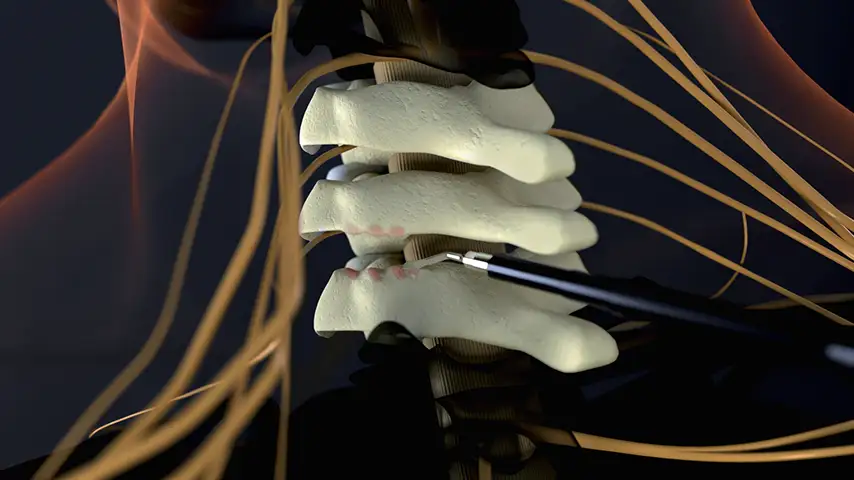

Selective osteotomies, safety on soft tissues

Laminotomy and Laminectomy

Correction of Deformities

Removal

of Osteophytes

Selective cut preserves soft tissue. (Dura, neves and vessels)

Cold osteotomy avoids bone necrosis

Increased surgical control & flexibility in bone cutting

Micrometric cut for minimal bone loss